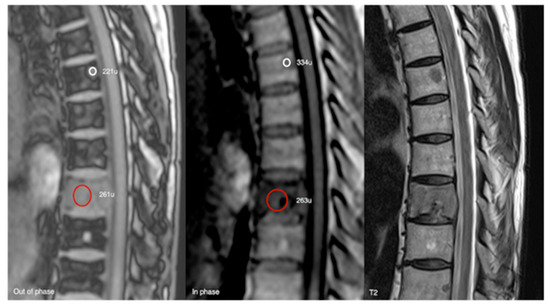

Figure 18.

Out-of-phase, in-phase, and T2 sagittal MRI spine as labelled on images (bottom left). Typical haemangioma, upper thoracic spine (221 SI vs. 334 SI), and biopsy-proven breast metastases, lower thoracic region (261 SI vs. 263 SI), with respective values on out-of-phase and in-phase imaging. The calculated signal dropout in the case of the typical haemangioma is 33.8 (>20%) and for breast metastasis it is 0.8 (<20%).